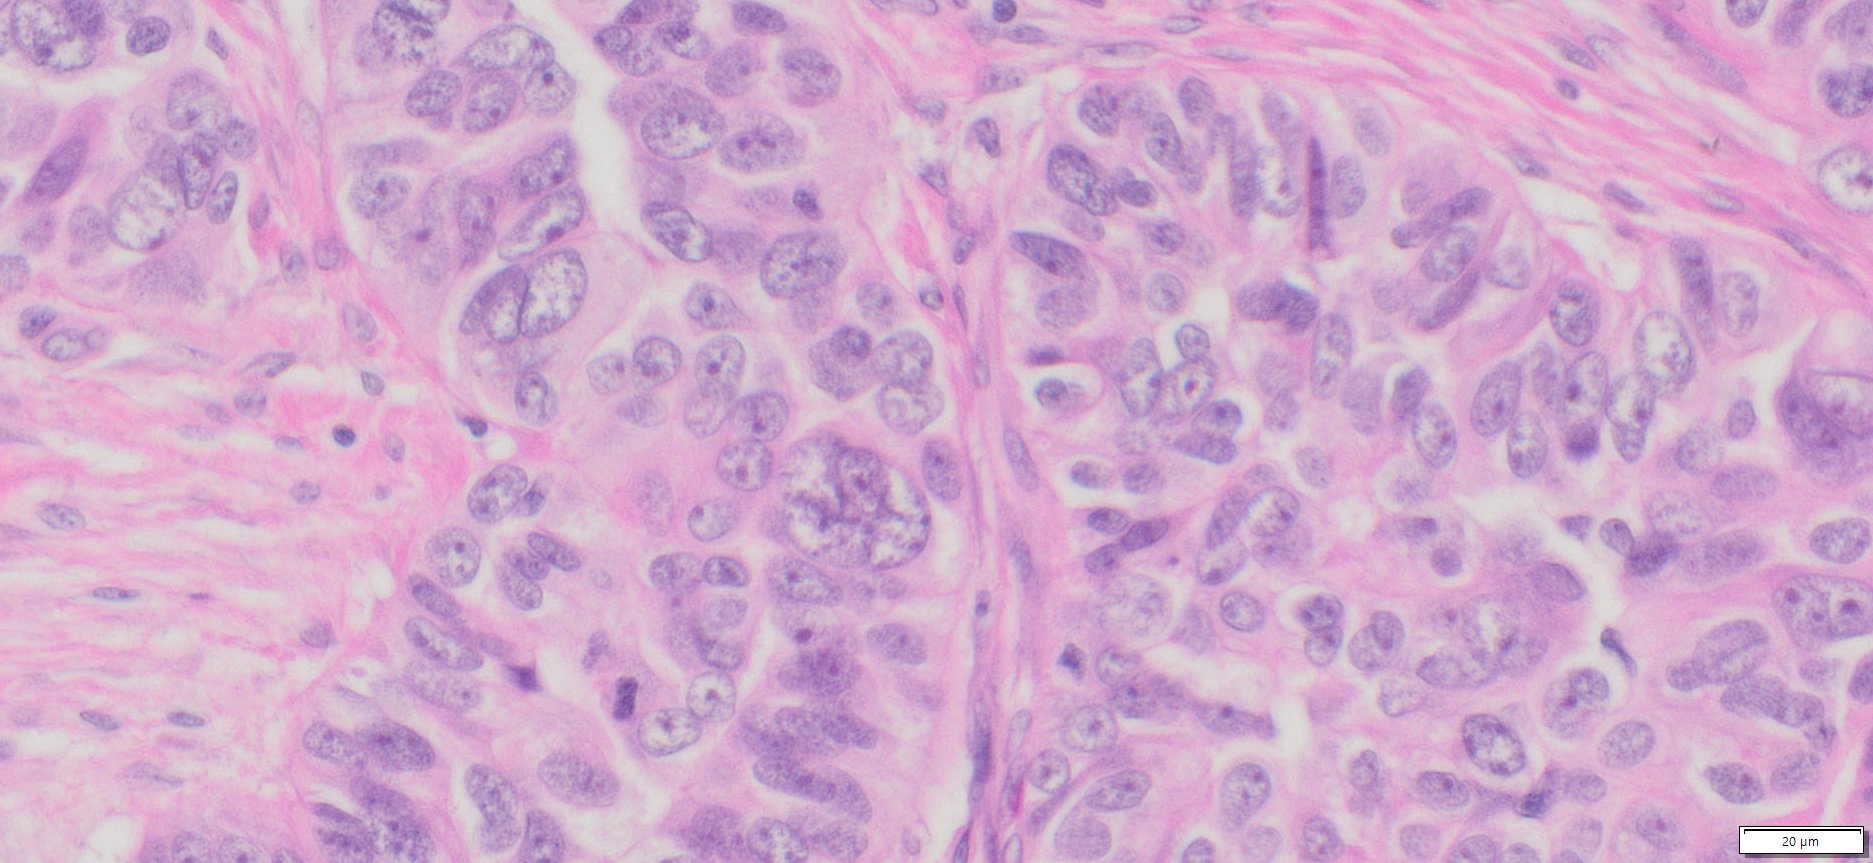

Description

| Organ& Tissue | Pathology Diagnosis | Gender/Age | % Tumor Area | Grade | TMN Stage | IHC Biomarkers |

| Human Ovary | High Grade Serous Carcinoma (HGSC) FFPE Sections | Female/67 | 80% | III | NA | ER(+),Pax-8 (+),WT-1(+),p16(+),p53(+),Ck7 (+), CK20(-) |